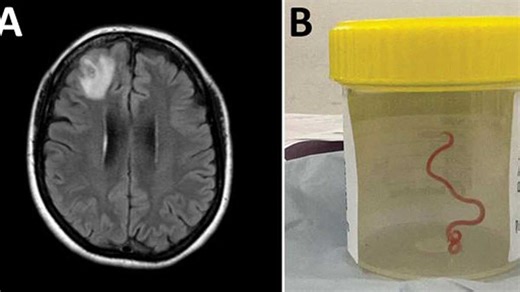

Parasitic worm found in woman’s brain in world first

'It’s alive and moving': Doctors remove 3-inch parasitic worm fro

Worm discovered living in woman’s brain in world’s first case: ‘It’s aliv